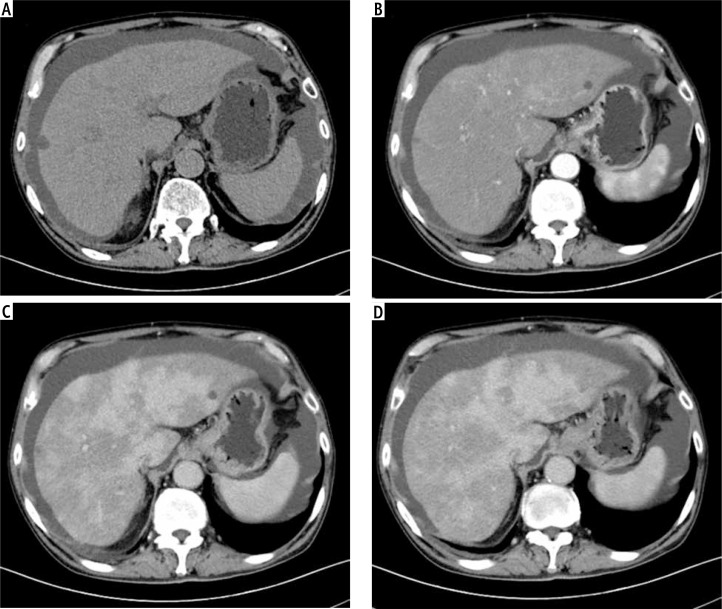

Abstract Image